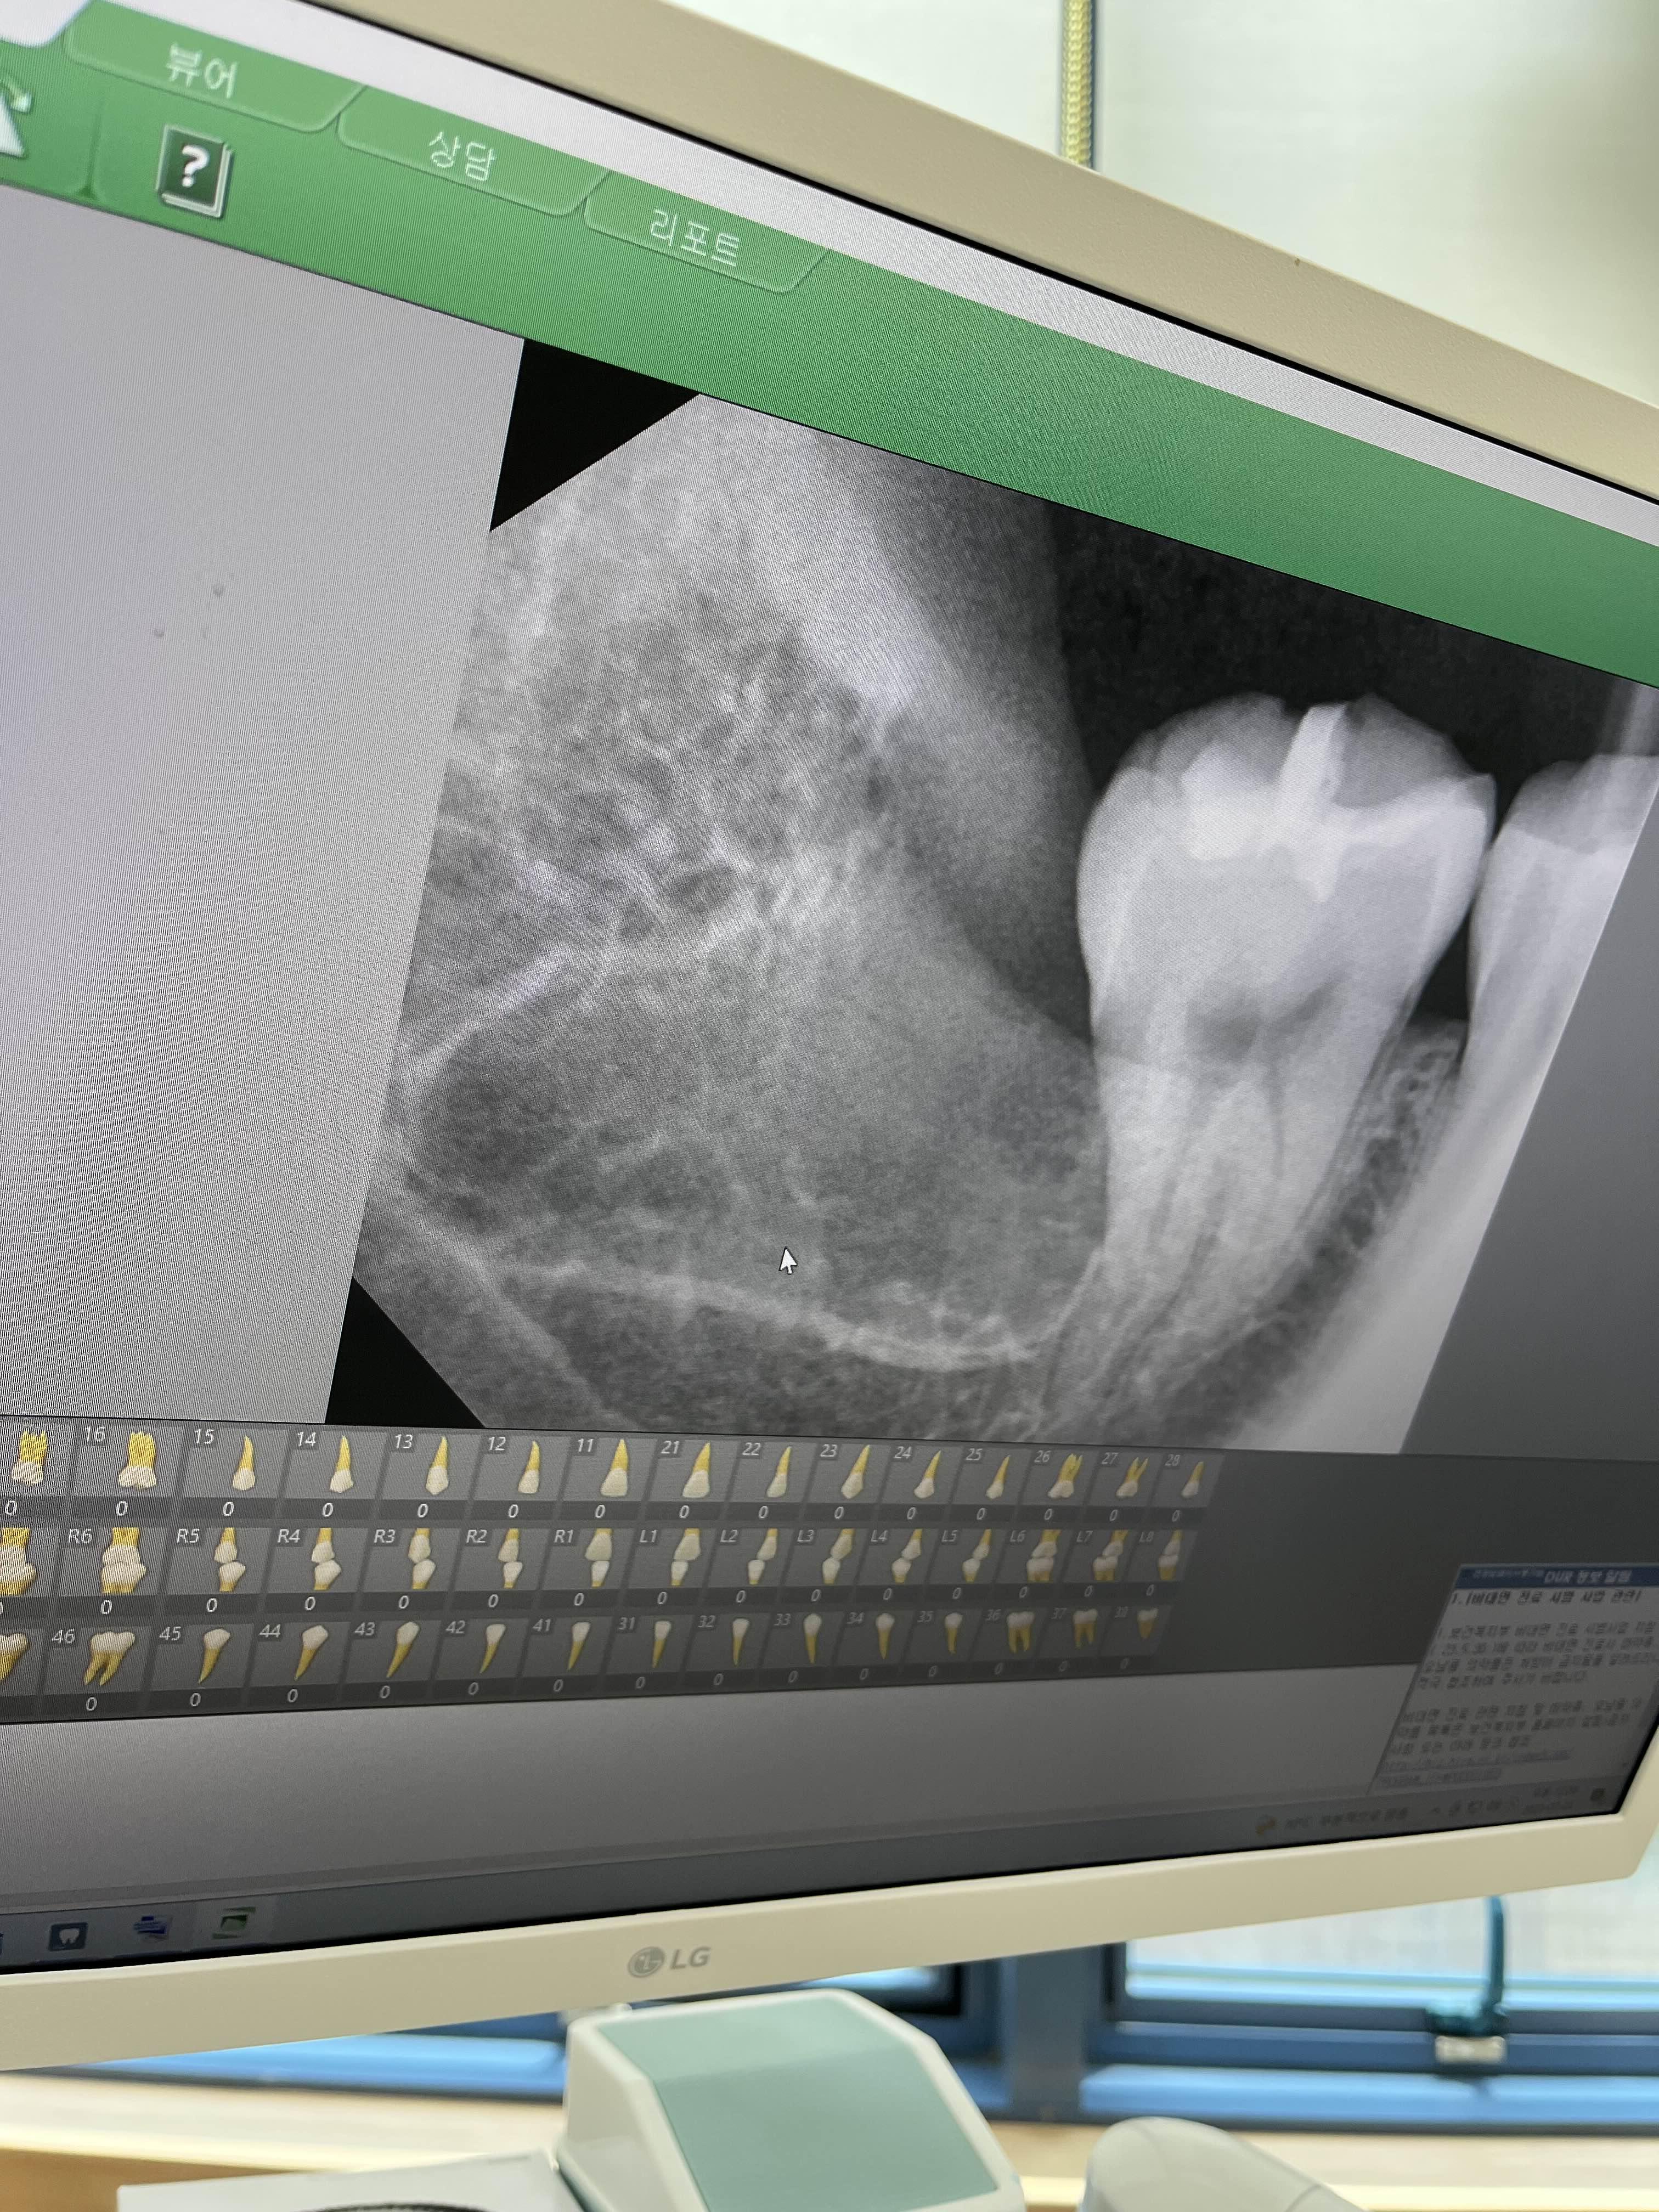

사랑니 마취가 다 됐는지 확인하시고 사랑니를 본격적으로 뽑기 시작했어요 잇몸을 찢고 뼈를 갈고 열심히 뽑아주셨는데 제가 피가 너무 많이 난다고...(불행 시작)의사 선생님이 시야 확보가 안된다고 엄청 노력해주셨는데 피 때문에 잘 안보여서 이 때 벌써 2시간 넘게 소요 됐어요 아무리 솜으로 막고 쉬는 타임 3번이나 가졌는데도 멈추지 않는 피...2시간 개고생을 하고 엑스레이를 한 번더 찍으로 갔는데..

세상에 2시간을 입술 찢어져가며 개고생을 했는데 저 만큼 남은거 보이시나요? 의사선생님이 분명 거의 다 됐다고 하셨는데 망할 사랑니

의사선생님이 사랑니 뽑으시면서 작은 소리로...또 있네 이럴때 알아 봤어야 하는데 제가 9시30에 방문했는데 12시쯤 됐었거든요 저거 보고 망연자실하고 1시에 점심시간인데 밥 못드실까봐 너무 걱정되고 많은 생각이 스쳐지났어요 그래도 의사선생님이랑 위생사 선생님이 열심히 열심히 위생사 선생님은 피를 잘 제거해주시고 의사 선생님도 열심히 사랑니와 사투를 하셔서 3시간만에 사랑니를 다 뽑았습니다 뽑기 넘 힘드셨는 지 다른 쪽으로 찢으셔서 그 부분이 밥 먹을 때마다 걸리적 거려요 ㅜ 어쨌든 마무리로 실로 봉합해주시는데 마취가 거의 다 풀려서 생살을 꿰매는 기분이 너무 들어서 온몸을 사시나무처럼 떨어대니 마취를 더 넣어주셨어요 마취를 더 넣기 싫어서 참았는데...제길